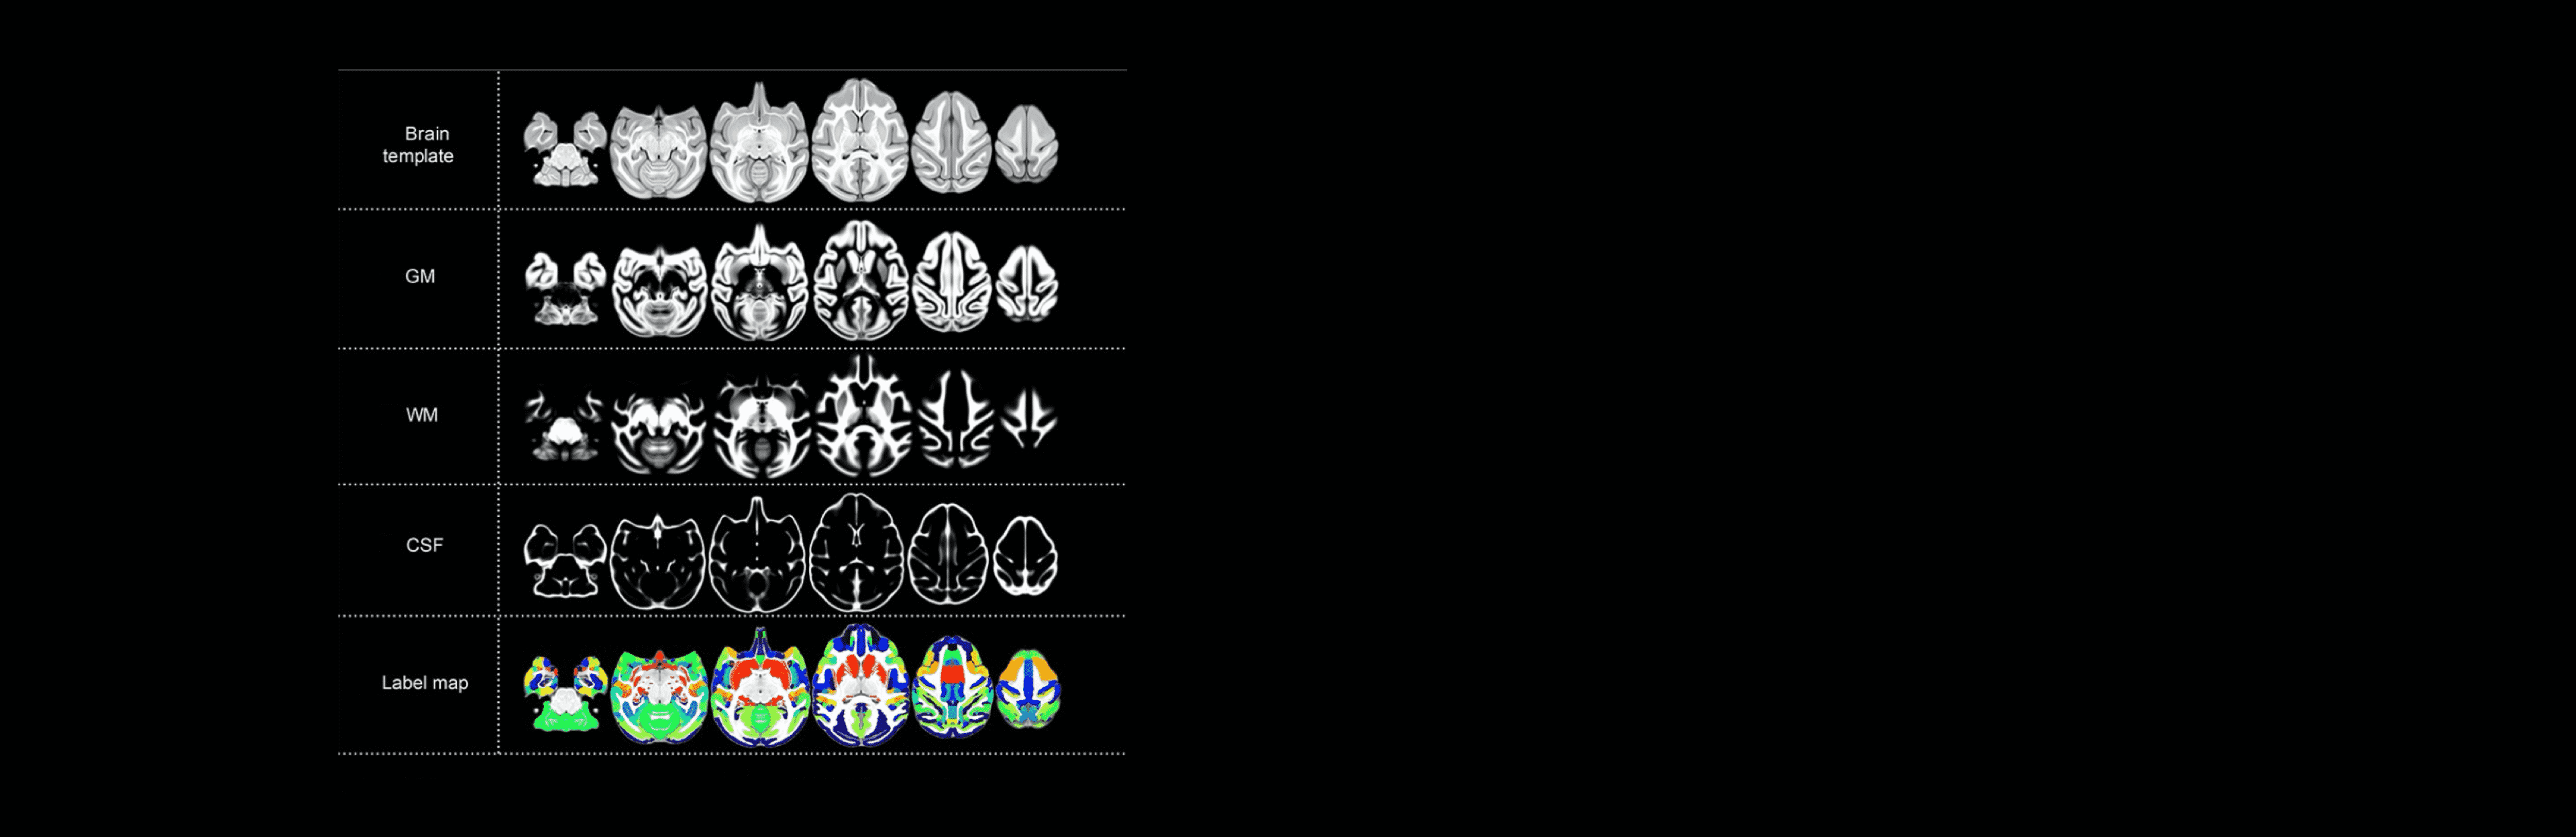

基于联影医疗高端科研型3.0T磁共振、定制猴脑定位仪与线圈,中国科学院昆明动物研究所制作了大样本食蟹猴脑图谱标准化模型,为脑科学领域重大疾病机理研究、治疗及干预技术研究开启无限可能。